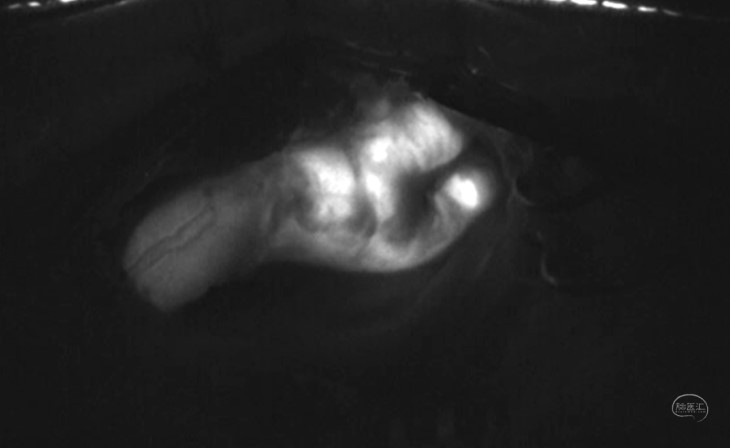

颈动脉内膜剥脱术